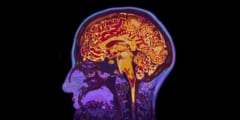

がん患者がアルツハイマー病を発症しにくい理由が見えてきた - ナゾロジー